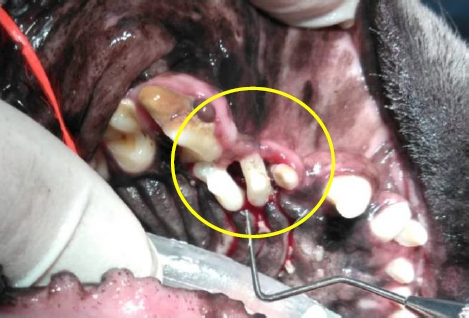

上左写真がスケーリングをした後の口腔鼻腔瘻管になっている部分です。歯と歯のすき間がかなり広がり、見た目にも大きな穴が空いているようにも見えます。実際にその部分の抜歯をしますと、上右写真のようにたくさんの膿が溜まっていて、それを全て掻き出している状態です。

上写真がスケーリングをした後の口腔鼻腔瘻管になっている部分です。歯と歯のすき間がかなり広がり、見た目にも大きな穴が空いているようにも見えます。実際にその部分の抜歯をしますと、下写真のようにたくさんの膿が溜まっていて、それを全て掻き出している状態です。